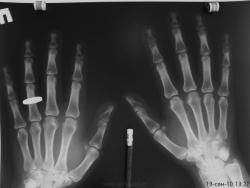

Сотрудница того же травм.пункта) лет 50. сразу извиняюсь за качество снимков. беспокоят боли в суставах кистей. меня заинтересовала структура кости в области ногтевых фаланг- уплотнение структуры, ногтевые фаланги смотрятся плотными. подобные изменения видел часто, но не в такой степени выраженности. может кто знает природу этого уплотнения и когда это встречается. и вообще - норма или нет. заранее благодарен.

это возрастные изменения в Рейнберге подробное описание,- я по поводу склероза; ну и кистовидная перестройка её как признак доа